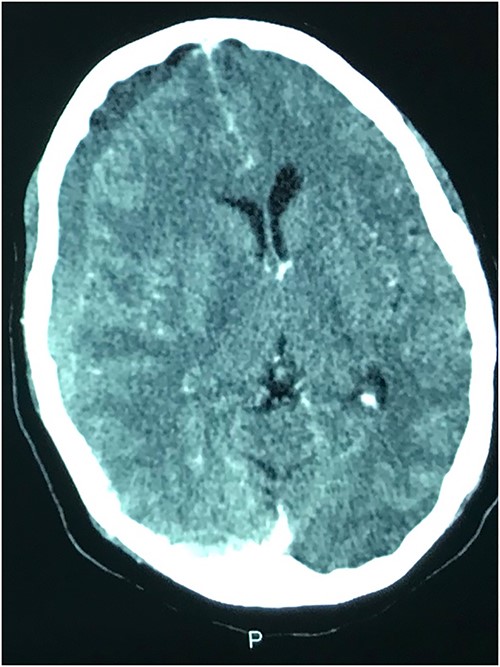

Case 2 – paraplegia

A 72-year-old man who was admitted by the orthopaedic team on account of progressive lower extremity weakness of 3 weeks duration that culminated in his inability to ambulate independently. He had no other neurologic symptoms. He denied history of prior trauma. Although he was a known hypertensive, he had not been on antiplatelets. His neurologic examination revealed a fully conscious elderly man who was awake, alert, well oriented in time, place, and person. Other neurologic examination findings were normal except for grade 2 power in both lower limbs. His deep tendon reflexes were normal in all extremities. Sensory function was intact.

Prior to this, he had been managed for low back pain and lumbar spondylosis. Spine MRI done prior to neurosurgery consultation did not explain the lower extremity motor weakness. Brain CT done revealed bilateral fronto-parietal CSDH (Fig. 2A). He was worked up for urgent surgical evacuation through a bilateral frontal and parietal burr hole drainage. He made good neurologic improvement and his lower extremity power returned to normal on the 8th day post op. Post-operative CT scan done at 4 weeks follow-up showed satisfactory resolution of the haematoma (Fig. 2B).

(A) Pre-op showing bilateral CSDH. (B) Post op complete resolution of CSDH.